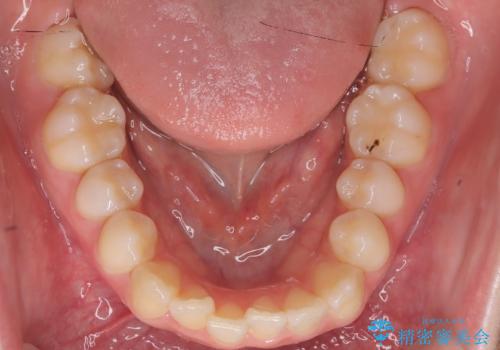

- 右上の前歯(2番)が下の歯より内側に入っている反対咬合を主訴にご来院されました。精密な検査の結果、この反対咬合を解消するためには、右上の歯列に前歯を出すためのスペースを確保する必要があると判明しました。患者様のご希望に合わせ、透明で目立たないインビザライン(マウスピース矯正)による治療計画を立案。奥歯全体を奥へ動かす遠心移動でスペースを作り、反対咬合を解消することを目指します。

今回の矯正治療では、透明なマウスピース型の装置インビザラインを使用しました。治療は、緻密なデジタル計画に基づき、奥歯から順に歯列全体を後方へ移動させる遠心移動を実施し、前歯を前に出すためのスペースを確保しました。このスペースを利用して、内側に入り込んでいた右上2番をスムーズに前方に誘導し、正常な咬み合わせへと改善。目立たないインビザラインで、機能的な咬み合わせと美しい前歯の並びを獲得していただけました。